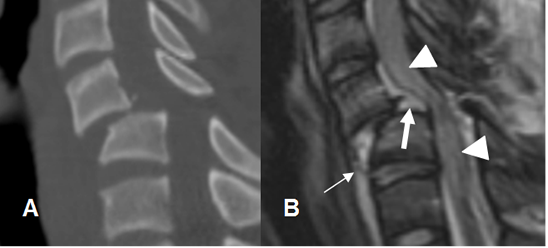

Fig 176 A. Lesión ligamentaria.

A: RM sagital en T2 y B: RM sagital en STIR. Luxación de facetas articulares, con anterolistesis de C5, sobre C6. Ligamento común anterior rodeado por líquido, pero permanece íntegro. (Flechas delgadas). Interrupción de los ligamentos común posterior y amarillo, por ruptura. (Flechas gruesas). Edema en los tejidos blandos posteriores, por lesión de los ligamentos interespinosos.

(Puntas de flecha.). Se aprecia escaso líquido anterior al cuerpo de C6.

Fig 176 B. Lesión ligamentaria.

A: TAC reconstrucción lateral y B: RM sagital en T2. Anterolistesis traumática, con aumento del espacio retrofaringeo y colección anterior. Adelgazamiento del ligamento común anterior (Flechas delgada) y ruptura del posterior. (Flecha gruesa). Adicionalmente hay compresión y alteración en la señal medular, por edema. (Puntas de flecha).